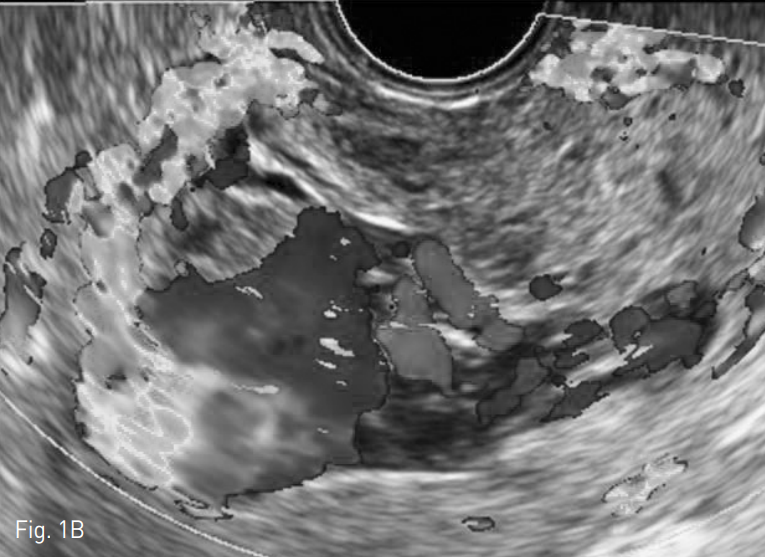

질식 초음파상에서 자궁에 큰 혈관성 종괴가 발견되었다. 종괴 내부에는 무에코성의 불규칙적인 관상 구조물이 관찰되었는데 이들은 색도플러 초음파에서 여러 방향의 빠른 속도를 보이는 동맥혈류를 가진 혈관 덩어리였다 (Fig. 1). 이후 복부전산화 단층촬영을 시행하였고, 자궁의 앞쪽 벽과 자궁강을 침범하는 장경 8cm 크기의 종괴를 확인할 수 있었다. 종괴 내부에는 비정상적인 혈관으로 보이는 구불구불한 관상의 조영증강 구조물들이 있었고, 자궁주변에 동맥기에서 조기 조영증강을 보이면서 비정상적으로 비대해져 있는 정맥도 관찰되었다 (Fig. 2).

Fig. 1

A. Gray scale transvaginal US shows a large intramyometrial mass with anechoic structures.

B. Color Doppler study shows tur bulent flow wi thin the anechoic structures.